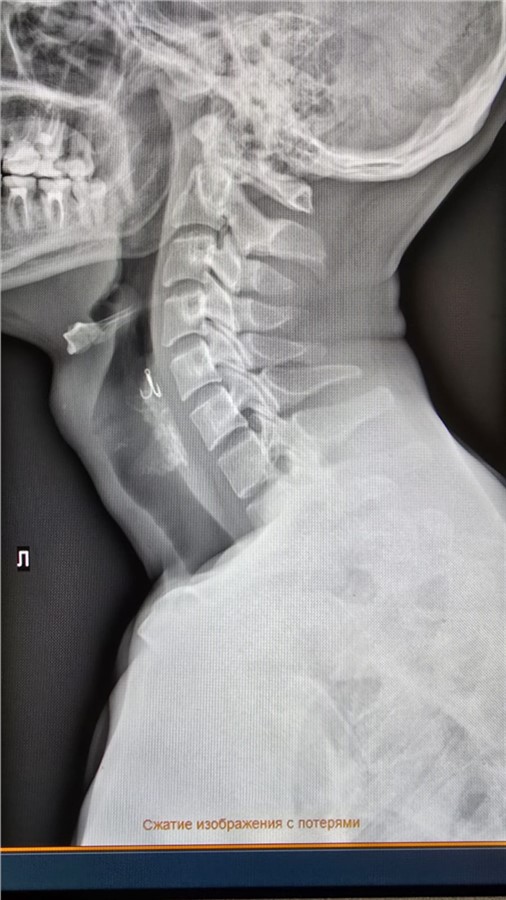

Врачи Красноярской краевой клинической больницы оказали помощь мужчине, который проглотил рыболовный крючок.

«Рыбак держал крючок во рту, стоя в лодке. В какой-то момент из-за сильного ветра она качнулась, толчок — и он рефлекторно сделал глотательное движение. Так крючок оказался в пищеводе», — поясняют медики.

Эндоскописты извлекли крючок без хирургических манипуляций — с помощью аппарата ФГС и щипцов.